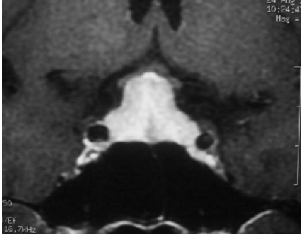

脑垂体瘤严重吗?垂体瘤是在鞍区较常见的良性肿瘤。其发病率为8.2-14.7 / 100000,占全部颅内肿瘤的10%-15%。就患病率而言,垂体瘤仅次于胶质细胞瘤和脑膜瘤。按照功能分类,可分为功能性和非功能性垂体瘤,非功能性垂体瘤更为常见。那些直径> 1 cm的垂体被定义为大的垂体瘤。垂体瘤的主要临床表现是荷尔蒙紊乱和肿瘤体积增加,从而导致头痛,视野障碍,颅神经损伤和生活质量降低。除泌乳性垂体瘤外,手术切除是优选治疗方法,大多数垂体瘤可通过经蝶窦手术切除。目前,在显微镜和神经内镜下经蝶窦入路切除垂体瘤是一种临床成熟的微创手术。脑垂体瘤严重吗?神经内镜和显微经蝶窦入路切除非功能性垂体瘤

垂体瘤的治疗包括药物治疗,外科手术和放射治疗。催乳素瘤是较常见的分泌激素垂体瘤类型,优选多巴胺受体激动剂(例如溴隐亭)。Cabergo-line用于对溴隐亭有抗药性的患者。多巴胺受体激动剂可以减少激素水平和肿瘤大小。但是,症状无法缓解或复发的患者可以选择手术。对于药物疗效差的其他类型的垂体瘤,应优选手术切除。放射疗法是垂体瘤的辅助疗法,可减少肿瘤大小并降低手术难度。它还可以帮助治疗残留和复发的垂体瘤。因此,手术是非功能性垂体瘤的主要治疗方法。在显微镜和神经内镜下通过蝶窦入路切除垂体瘤是一种临床成熟的微创手术。

经鼻蝶手术入路发展至今已有100多年的历史。通过手术技术及器械的改进,神经内镜下经鼻蝶入路已成为目前神经外科重要的手术方式。在过去的20年中,神经内镜经蝶窦切除垂体瘤的方法在国内得到了迅速的发展。可以通过神经内镜镜观察病变组织及其周围结构的各个方面。手术视野清晰,可以在手术过程中清楚地识别鞍座及其周围的解剖结构。可以清楚地观察到肿瘤切除,并且可以减少死角。同时,我们可以更好地避免损伤颈内动脉,海绵窦,视神经和动眼神经。患者遭受的损伤更少,从而减轻了术后康复。